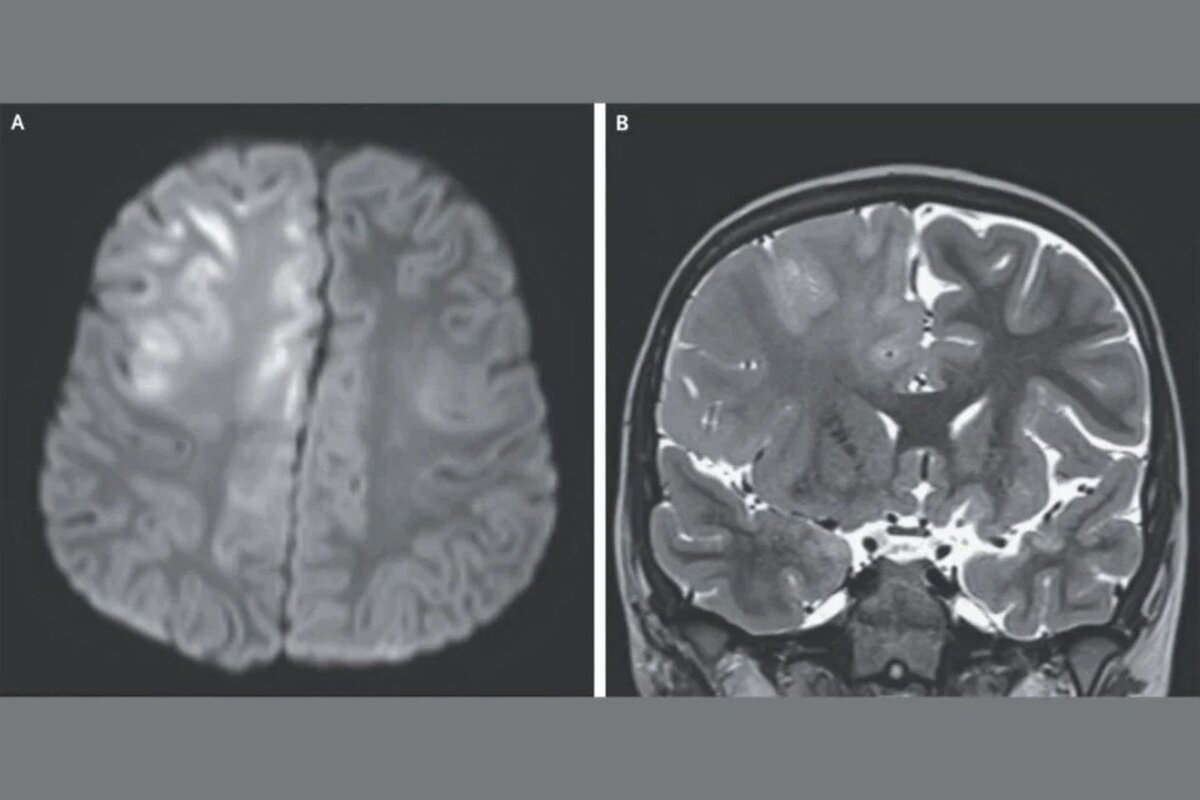

En el caso descrito, el niño acudió al médico tras tres meses de convulsiones y deterioro cognitivo. Había perdido la capacidad de hablar y la resonancia magnética evidenció un daño cerebral extenso. Había contraído sarampión a los siete meses de edad mientras vivía en Afganistán, donde el virus es endémico. El análisis del líquido cefalorraquídeo mostró niveles elevados de anticuerpos contra el virus, y junto con el antecedente clínico y los hallazgos del electroencefalograma, se confirmó el diagnóstico de panencefalitis esclerosante subaguda. Doce meses después de los primeros síntomas, el niño falleció.